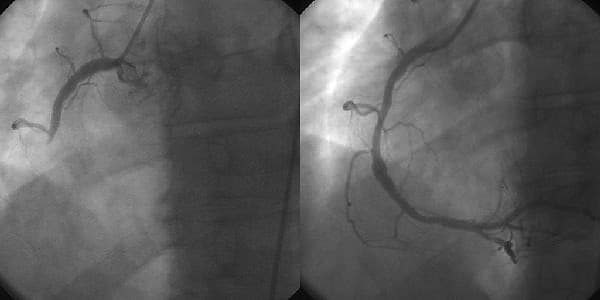

Interventional cardiology is a branch of cardiology that deals specifically with the catheter based treatment of structural heart diseases. Andreas Gruentzig is considered the father of interventional cardiology after the development of angioplasty by interventional radiologist Charles Dotter. Many procedures can be performed on the heart by catheterization. This most commonly involves the insertion of a sheath into the femoral artery (but, in practice, any large peripheral artery or vein) and cannulating the heart under X-ray visualization (most commonly fluoroscopy). The radial artery may also be used for cannulation; this approach offers several advantages, including the accessibility of the artery in most patients, the easy control of bleeding even in anticoagulated patients, the enhancement of comfort because patients are capable of sitting up and walking immediately following the procedure, and the near absence of clinically significant sequelae in patients with a normal Allen test. Downsides to this approach include spasm of the artery and pain, inability to use larger catheters needed in some procedures, and more radiation exposure. But, in recent times radial approach is getting popularity due to its patient comfort after procedure. The main advantages of using the interventional cardiology or radiology approach are the avoidance of the scars and pain, and long post-operative recovery. Additionally, interventional cardiology procedure of primary angioplasty is now the gold standard of care for an acute myocardial infarction. It involves the extraction of clots from occluded coronary arteries and deployment of stents and balloons through a small hole made in a major artery, which has given it the name "pin-hole surgery" (as opposed to "key-hole surgery"). Angioplasty is an intervention to dilate either arteries or veins. Percutaneous coronary intervention (PCI/Coronary angioplasty)the use of angioplasty for the treatment of obstruction of coronary arteries as a result of coronary artery disease.